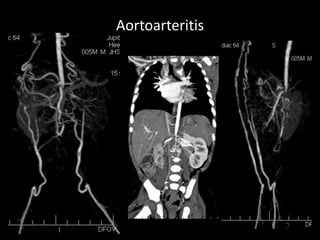

Aortoarteritis

• K/c/o Erythema nodosum with

intermittent cluadication in both

lower limb.

• CT Angiogram of both lower limb:

• Rt lower limb- There is 1cm sized

significant stenosis (65-70%) of

proximal right common iliac

artery due to concentric

noncalcific wall plaque. It is

approx 2.8 cms from it’s origin.

• Lt lower limb- There is mild focal

narrowing (30%) at the origin of

left common iliac artery due to

eccentrically placed irregular

noncalcific plaque.

• 3.7X6.1X5.5 cms sized

pseudoaneurysm is seen at

the site of distal

anastomosis of the graft

with the popliteal artery.

• There is small eccentric

fusiform dilatation of upper

abdominal aorta. Stent is

seen in situ in bilateral renal

artery with no instent

restenosis.